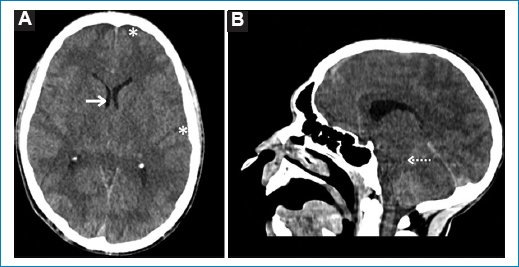

Respecto a los cinco pacientes con hallazgos patológicos agudos en la TCC, cuyas características demográficas y clínicas se describen en la tabla 2, se reconocieron un ACV isquémico agudo en el territorio de la arteria cerebral media derecha (Fig. 1), un edema cerebral difuso por encefalitis (Fig. 2), una encefalopatía necrotizante aguda (Fig. 3) y dos hematomas intracraneales intraaxiales, de los cuales uno en se ubicó en los núcleos de la base del hemisferio cerebral izquierdo y el otro en el lóbulo parietal derecho (Fig. 4). Todos ellos correspondieron a cuadros de dengue grave.

Figura 4. Imágenes axiales de TCC de dos pacientes varones con hematomas intracraneales agudos (asteriscos). (A) Paciente de 50 años con hematoma en los núcleos de la base del hemisferio cerebral izquierdo. (B) Paciente de 47 años con hematoma lobar parietal derecho.